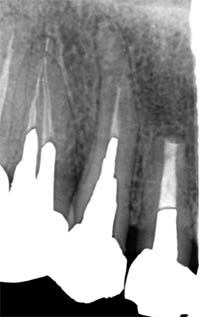

根尖封鎖の比較

![]() |

| MTA根充前 | MTA根充後 |